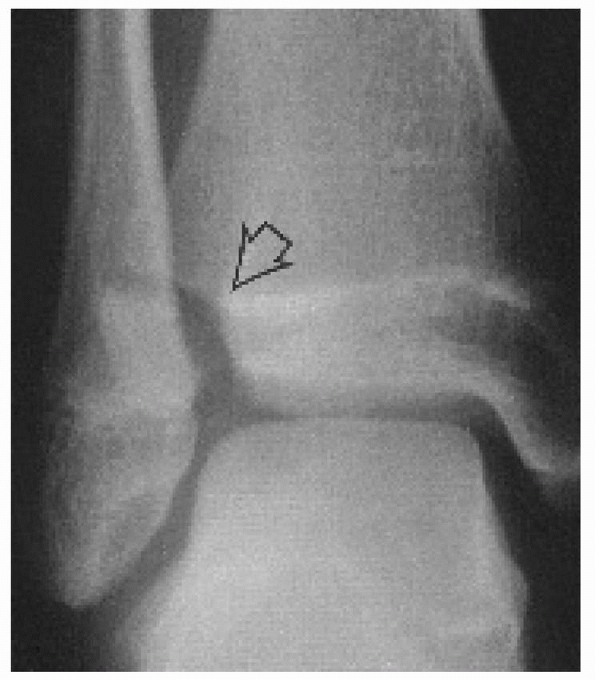

on standard radiographs, but the size of the fragment is smaller than

that typically seen with the Tillaux fractures (Fig 26-13).44 On the CT scan, this fracture does not extend to the anterior cortex of the distal tibia (Fig 26-14).

The mechanism of injury may be an avulsion of the fragment by the

interosseous ligament. This may be a variant of an adult tibia-fibular

diastasis injury.